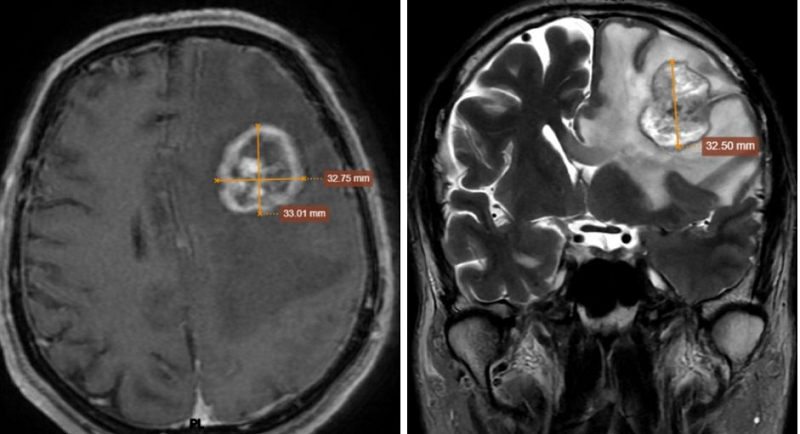

Hình ảnh MRI sọ não phát hiện một khối choán chỗ tại vùng thái dương - đỉnh trái với kích thước khoảng 32mm. Không chỉ có một khối u đơn độc, não còn xuất hiện nhiều tổn thương rải rác ở cả hai bán cầu và màng não. Tình trạng phù não lan rộng, gây chèn ép và đẩy lệch đường giữa gần 8 mm - đây là dấu hiệu nguy hiểm, có thể ảnh hưởng trực tiếp đến tính mạng.

Chụp MRI sọ não có khối choán chỗ vùng thái dương - đỉnh trái, kích thước 32x33x32mm